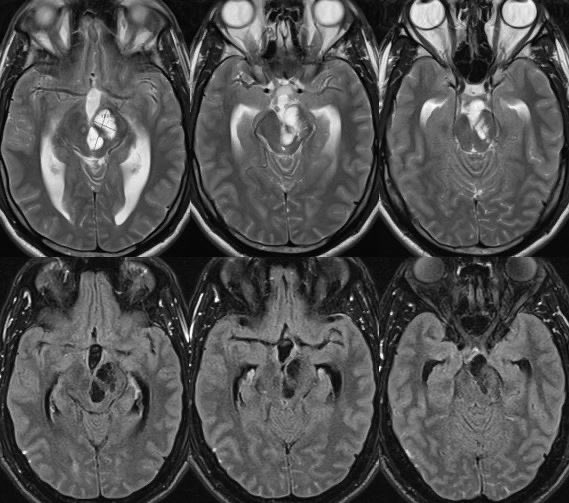

What is the most likely diagnosis in this 30 y/o M presenting with headaches? 🧠